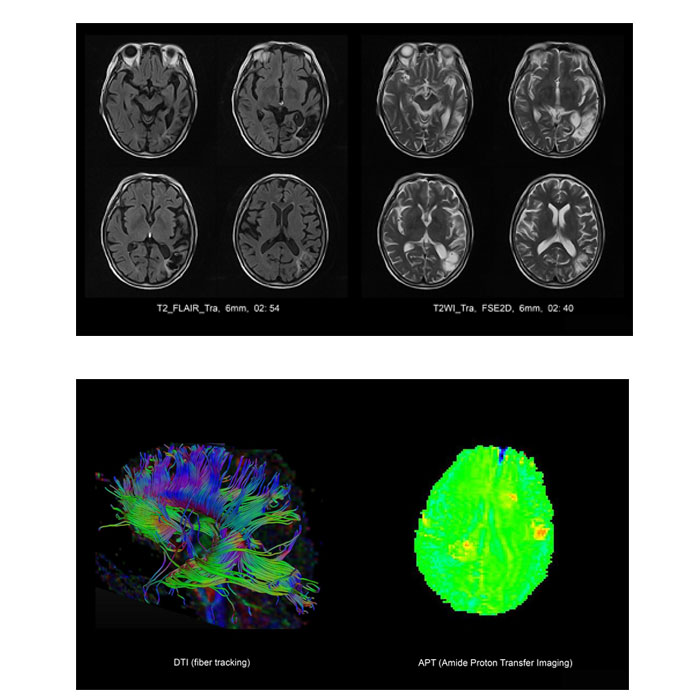

4.1 Brain Imaging

T1WI, T2WI, FLAIR, HD-DWI, ADC, A-SWI, 3D-TOF MRA, 3D-TOF MRV, T1WI-C+ (T2WI slice thickness=2mm)

- APT* (Amide Proton Transfer Imaging): Advanced functional application (available on request)